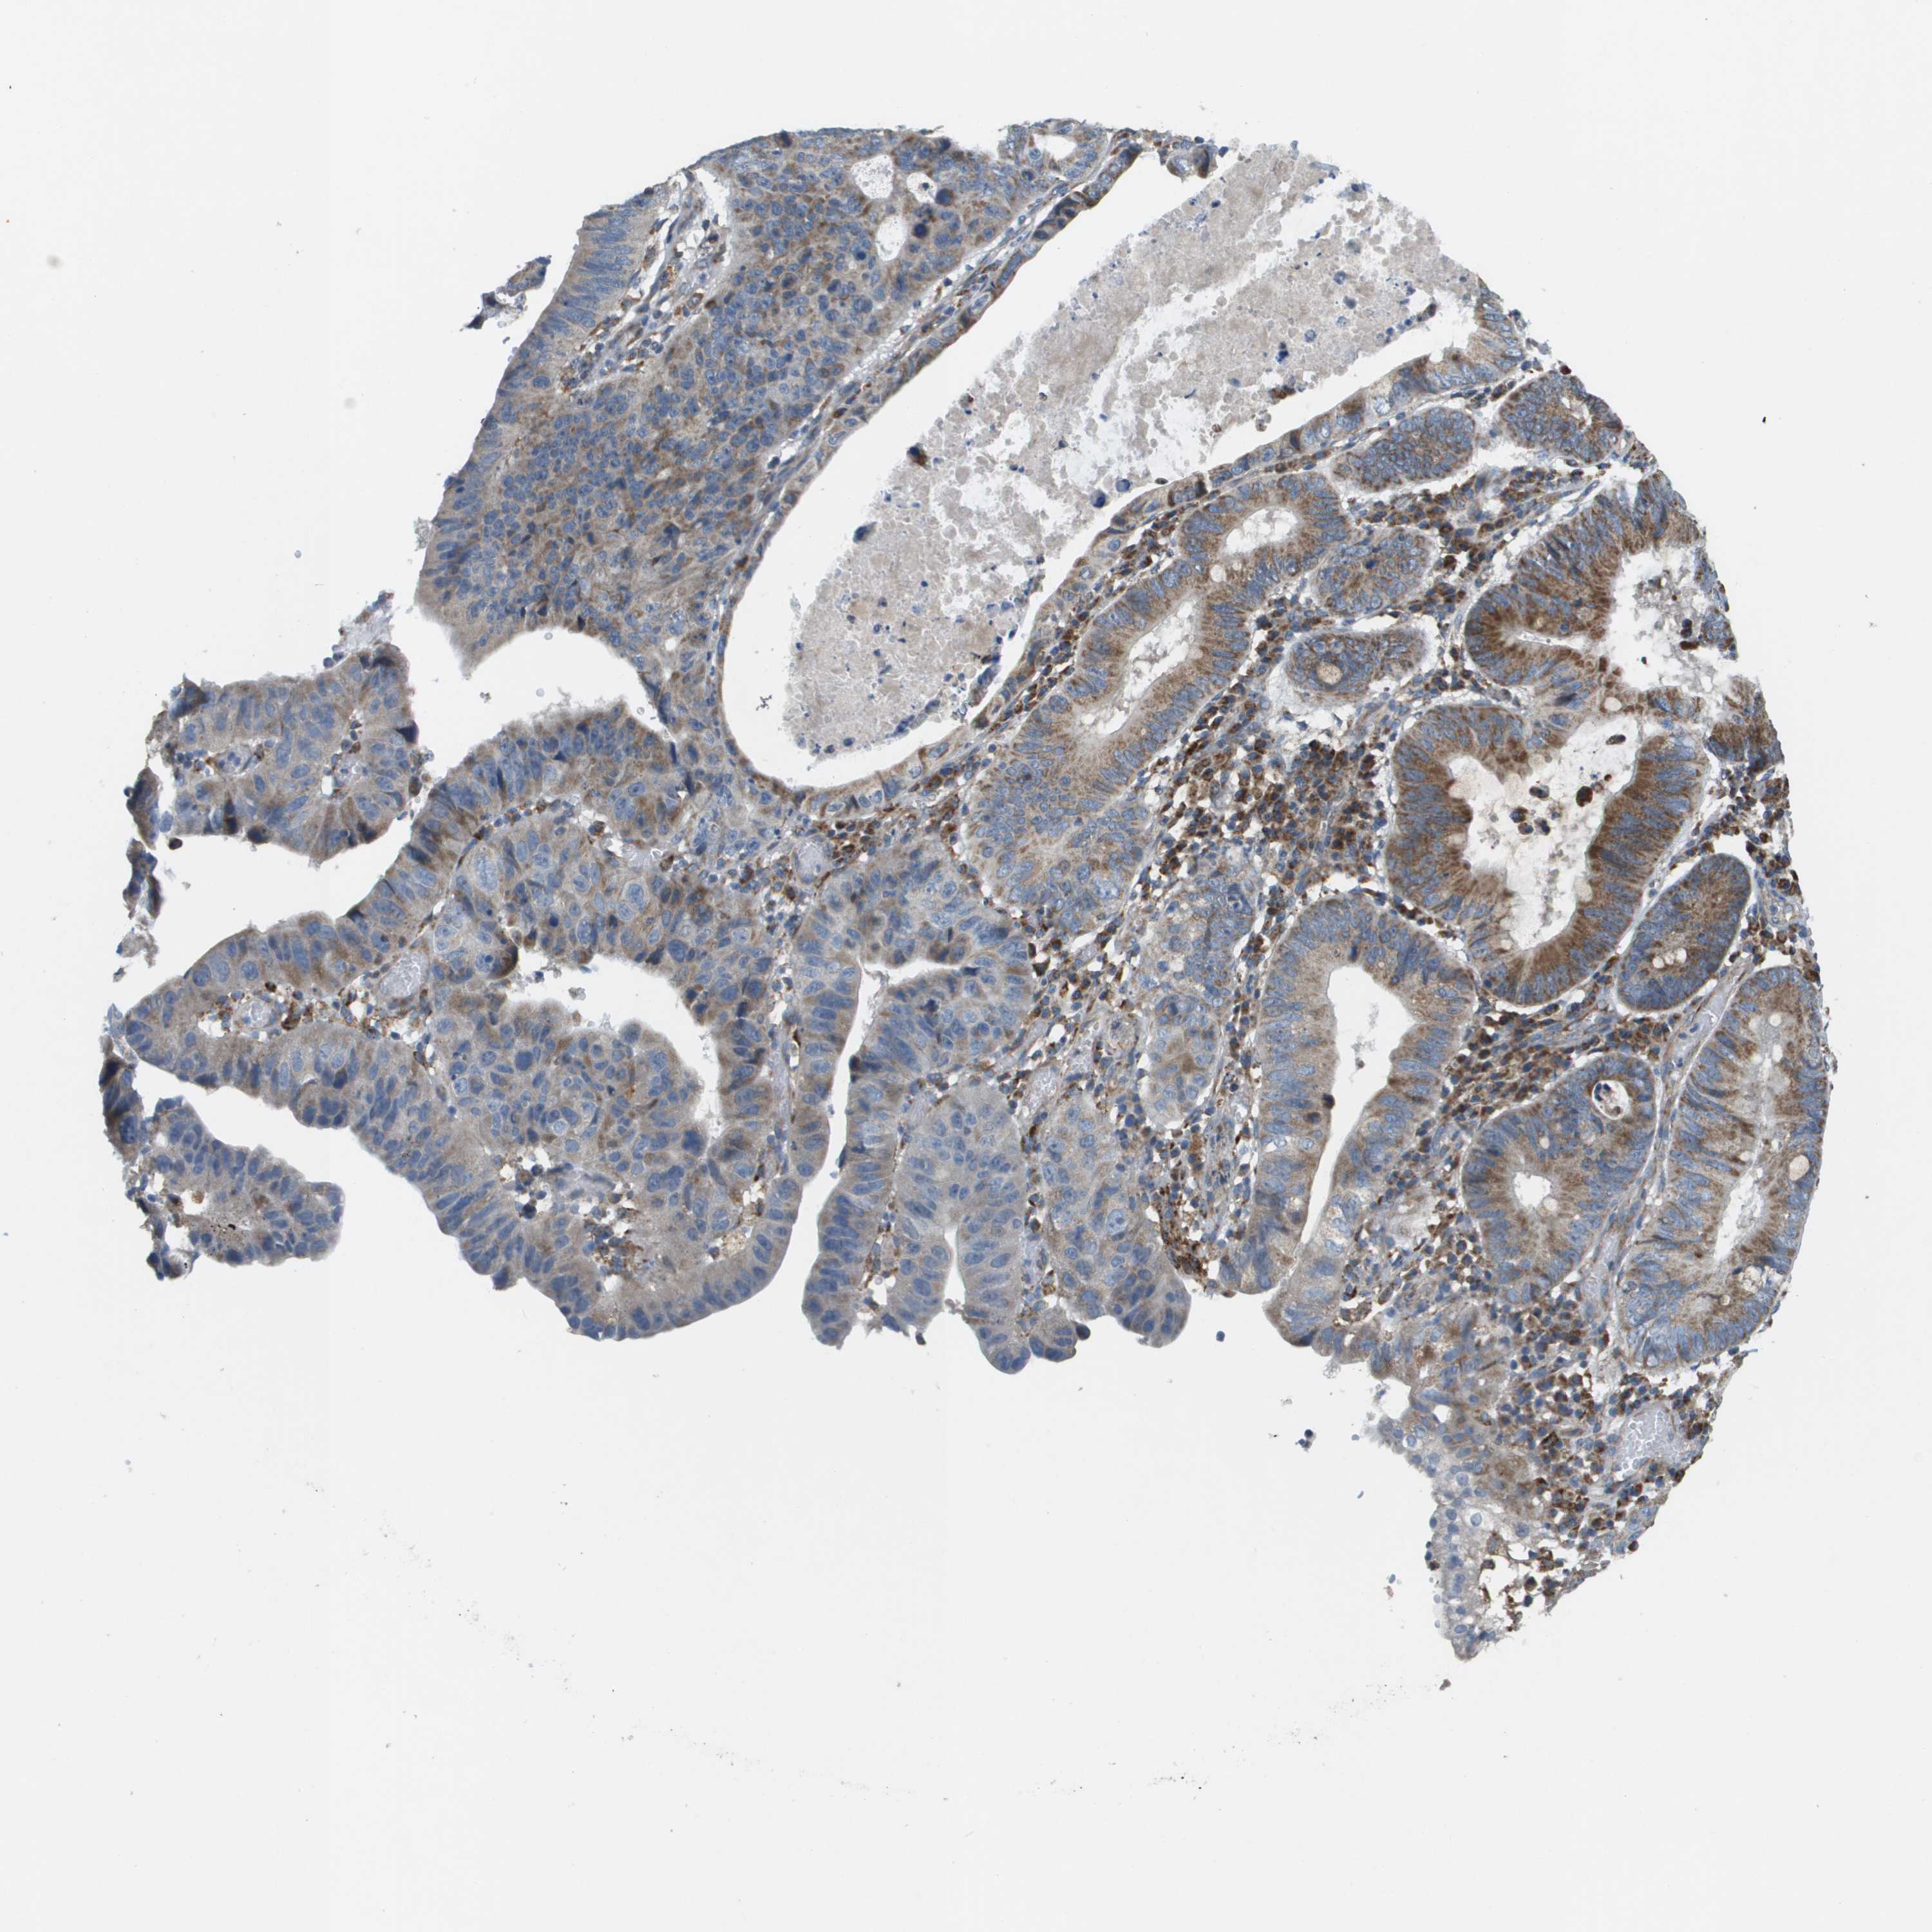

STOMACH CANCER - Protein expressioni

A mouse-over function shows sample information and annotation data. Click on an image to view it in a full screen mode. Samples can be filtered based on level of antibody staining by selecting one or several of the following categories: high, medium, low and not detected. The assay and annotation is described here.

Note that samples used for immunohistochemistry by the Human Protein Atlas do not correspond to samples in the TCGA dataset.

Antibody stainingi

Antibody staining in the annotated cell types in the current human tissue is reported as not detected, low, medium, or high, based on conventional immunohistochemistry profiling in selected tissues. This score is based on the combination of the staining intensity and fraction of stained cells.

Each image is clickable and will lead to virtual microscopy that enables deeper exploration of all samples and also displays staining intensity scores, fraction scores and subcellular localization as well as patient and tissue information for each sample.

Antibody HPA017238

Staining

High

Medium

Low

Not detected

Intensity

Strong

Moderate

Weak

Negative

Quantity

>75%

75%-25%

<25%

None

Location

Nuclear

Cytoplasmic/membranous

Cytoplasmic/membranous,nuclear

Adenocarcinoma, NOS